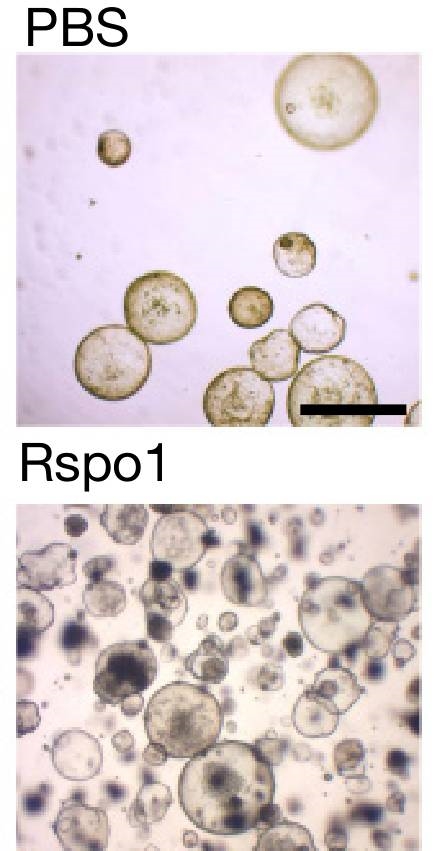

ÕÉīµŚČ�’╝ī�’╝ī’╝ī’╝ī�’╝ī’╝ī�’╝īMeyerÕŹÜÕŻ½Ķ┐śÕÅæµśÄ�’╝ī�’╝ī’╝ī’╝ī�’╝ī’╝ī�’╝īÕĮōÕ╣ĮķŚ©Ķ×║µØåĶÅīõŠĄÕģźµŚČ�’╝ī�’╝ī’╝ī’╝ī�’╝ī’╝ī�’╝īĶāāń▓śĶå£õĖŗµ¢╣ńÜäķŚ┤Ķ┤©µłÉń║żń╗┤ń╗åĶā×õ╝ܵĖŚķĆÅõĖĆń¦ŹÕÉŹõĖ║R-ĶäŖķ½ōÕŹĄńÖĮ’╝łRspo’╝ēńÜäńē®Ķ┤©�’╝ī�’╝ī’╝ī’╝ī�’╝ī’╝ī�’╝īõĮ£ńö©õ║ÄĶāāń▓śĶå£õĖŗµ¢╣Õ╣▓ń╗åĶā×µ▒Ā�’╝ī�’╝ī’╝ī’╝ī�’╝ī’╝ī�’╝īµ┐Ƶ┤╗Õ╣▓ń╗åĶā×ńÜäWNTķĆÜĶĘ»Ķ░āńÉåÕ╣▓ń╗åĶā×ńÜäÕó×µ«¢õ╗źÕ║öÕ»╣Õ╣ĮķŚ©Ķ×║µØåĶÅīńåŵ¤ōŃĆéŃĆéŃĆéŃĆéŃĆé

ÕÅ»µś»�’╝ī�’╝ī’╝ī’╝ī�’╝ī’╝ī�’╝īMeyerÕŹÜÕŻ½ÕÅæµśÄ�’╝ī�’╝ī’╝ī’╝ī�’╝ī’╝ī�’╝īĶ┐ÖõĖżń¦Źń╗åĶā×Õ»╣WNTķĆÜĶĘ»ńÜäÕÅŹÕ║öµś»ÕĘ«Õł½ńÜäŃĆéŃĆéŃĆéŃĆéŃĆ鵣ŻÕĖĖRspoõĮ£ńö©õ║ÄÕłåĶ¦Żµ░┤Õ╣│õĮÄ�’╝ī�’╝ī’╝ī’╝ī�’╝ī’╝ī�’╝īÕó×µ«¢ĶŠāÕ┐½ńÜäÕ╣▓ń╗åĶā×Õ£©ÕÉÄ�’╝ī�’╝ī’╝ī’╝ī�’╝ī’╝ī�’╝īõ╝ÜõĮ┐Õ╣▓ń╗åĶā×ńÜäÕó×µ«¢ķƤńÄ浜ŠĶæŚÕŖĀķƤ�’╝ī�’╝ī’╝ī’╝ī�’╝ī’╝ī�’╝īÕ»╝Ķć┤ÕģČÕż¬Ķ┐ćÕó×µ«¢ŃĆéŃĆéŃĆéŃĆéŃĆéĶĆīRspoõĮ£ńö©õ║ÄÕó×µ«¢ĶŠāµģóńÜäń╗åĶā×ÕÉÄ�’╝ī�’╝ī’╝ī’╝ī�’╝ī’╝ī�’╝īõ╝ܵśŠĶæŚµŖæÕłČÕģČÕó×µ«¢ŃĆéŃĆéŃĆéŃĆéŃĆé

Rspoõ╝ܵśŠĶæŚÕó×Õ╝║µĢŵä¤Õ╣▓ń╗åĶā×ńÜäµē®Õó×ķƤńÄć’╝łÕŹĢń╗åĶā×õĮ£Ķé▓24Õ░ŵŚČ’╝ē

µŁŻÕ”éSigalÕŹÜÕŻ½µēĆĶ»┤�’╝ī�’╝ī’╝ī’╝ī�’╝ī’╝ī�’╝ī“ńö▒õ║ÄÕ╣ĮķŚ©Ķ×║µØåĶÅīÕ╝ĢĶĄĘńåŵ¤ōµ£║õĮōµŚĀµ│ĢĶ欵łæµ▓╗µäł�’╝ī�’╝ī’╝ī’╝ī�’╝ī’╝ī�’╝īÕøĀµŁż�’╝ī�’╝ī’╝ī’╝ī�’╝ī’╝ī�’╝īĶŗźõĖŹµ▓╗ń¢Ś�’╝ī�’╝ī’╝ī’╝ī�’╝ī’╝ī�’╝īÕ╣ĮķŚ©Ķ×║µØåĶÅīÕÅ»ĶāĮµüÆõ╣ģõĖĆĶ┐×Õł║µ┐ĆķŚ┤Ķ┤©µłÉń║żń╗┤ń╗åĶā×µĖŚķĆÅRspoµØźÕł║µ┐ĆÕ╣▓ń╗åĶā×ńĀ┤ńóÄ�’╝ī�’╝ī’╝ī’╝ī�’╝ī’╝ī�’╝īĶ┐Öõ╣¤Ķ«ĖĶČ│õ╗źĶ»ĀķćŖõĖ║õ╗Ćõ╣łÕ╣ĮķŚ©Ķ×║µØåĶÅīńåŵ¤ōõ╝ܵśŠĶæŚÕó×µĘ╗ĶāāńÖīÕŹ▒Õ«│’╝ł10’╝ēŃĆéŃĆéŃĆéŃĆéŃĆé”